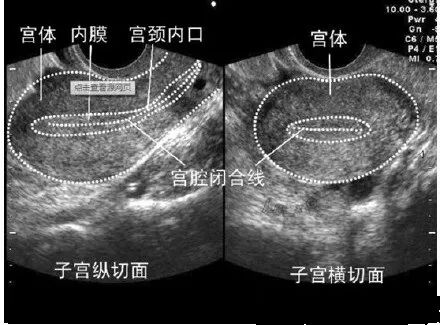

子宫内膜

子宫结构

子宫内膜是指构成子宫内壁的一层,分为致密层、海绵层和基底层3层。内膜表面2/3为致密层和海绵层统称功能层,受卵巢性激素影响发生周期变化而脱落。基底层为靠近子宫肌层的1/3内膜,不受卵巢性激素影响,不发生周期性的变化。